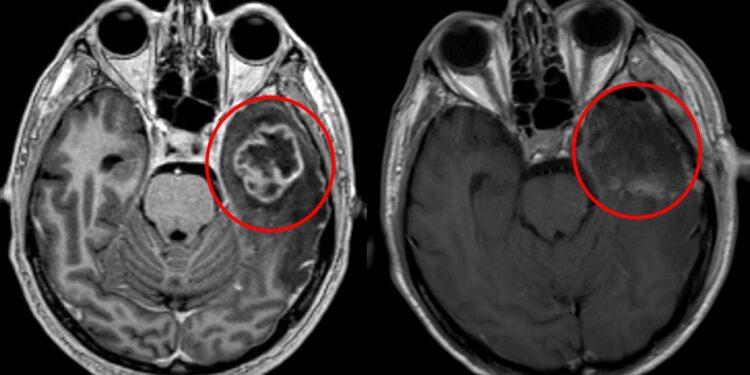

Per decenni i medici non sapevano cosa causasse questo tumore, perché non ha le mutazioni genetiche che si trovano negli altri cancri. Uno studio pubblicato ieri su Nature ha trovato una risposta inattesa: sono gli ormoni maschili. Il tumore si chiama ependimoma PFA, colpisce quasi sempre bambini sotto i cinque anni e uccide due su tre entro cinque anni dalla diagnosi. I maschi si ammalano più spesso delle femmine — e ora si sa perché. Gli androgeni, cioè il testosterone e ormoni simili, tengono le cellule tumorali in uno stato immaturo che le rende più aggressive e difficili da fermare. MedicalXpress Nei topi, bloccando questi ormoni il tumore cresce più lentamente. Farmaci che bloccano gli androgeni esistono già — si usano contro il cancro alla prostata negli adulti — ma somministrarli a neonati è un’altra cosa. Servono studi clinici appositi. Per ora i risultati sono solo in laboratorio, ma è la prima vera pista terapeutica che questo tumore abbia mai avuto.